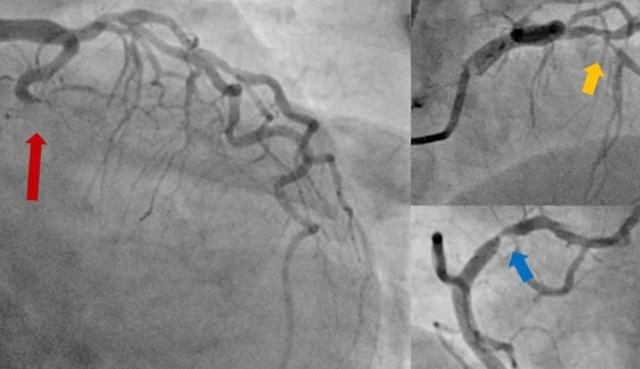

Người bệnh sau đó được đưa đến phòng DSA để được chụp động mạch vành cấp cứu. Kết quả chụp mạch vành cho thấy tắc hoàn toàn động mạch mũ, hẹp nặng động mạch liên thất trước và vành phải.

BS.CKI. Nguyễn Thanh Bình, Phó Trưởng khoa Nội Tim mạch nhận định: “Đây là trường hợp ngưng tim sau nhồi máu cơ tim, với thủ phạm là tắc hoàn toàn động mạch mũ, đồng thời hẹp nặng cả hai nhánh động mạch vành còn lại. Việc can thiệp tái thông hoàn toàn cả động mạch thủ phạm và hai động mạch hẹp nặng là phù hợp với các khuyến cáo hiện hành và sẽ giúp khả năng cứu được người bệnh cao hơn”.

Hình ảnh chụp động mạch vành cho thấy tắc hoàn toàn động mạch mũ (mũi tên đỏ), hẹp nặng cả động mạch liên thất trước (mũi tên vàng) và động mạch vành phải (mũi tên xanh).